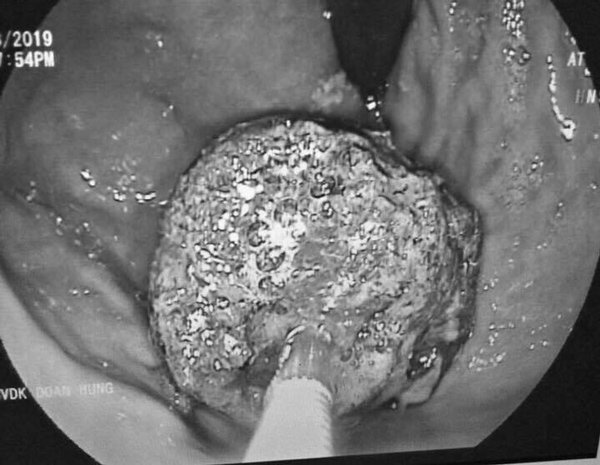

Khối bã thức ăn gây tắc ruột.

Người nhà bệnh nhân chia sẻ, L có thói quen ăn uống không khoa học, thường xuyên uống trà sữa, bỏ cơm. Sau khi được chẩn đoán các bác sĩ đã tiến hành mổ dạ dày, mở ruột lấy 2 khối bã thức ăn to trong dạ dày và ruột non.

Hình ảnh khối bã thức ăn được lấy ra sau khi các bác sĩ phẫu thuật.